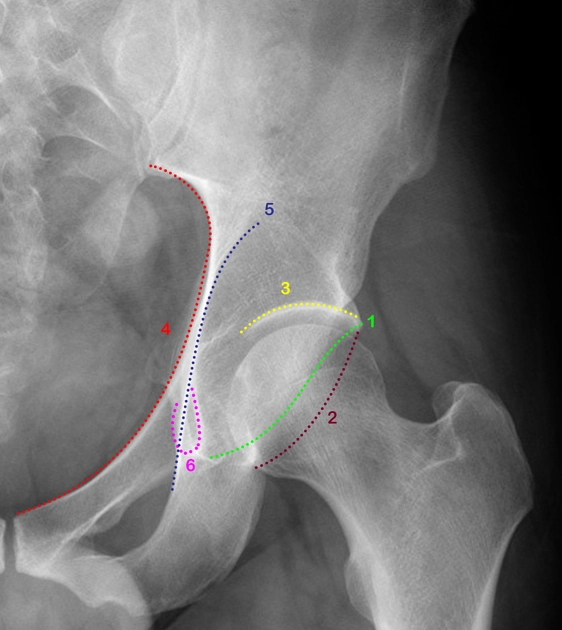

Tiếp cận X- quang xương chậu